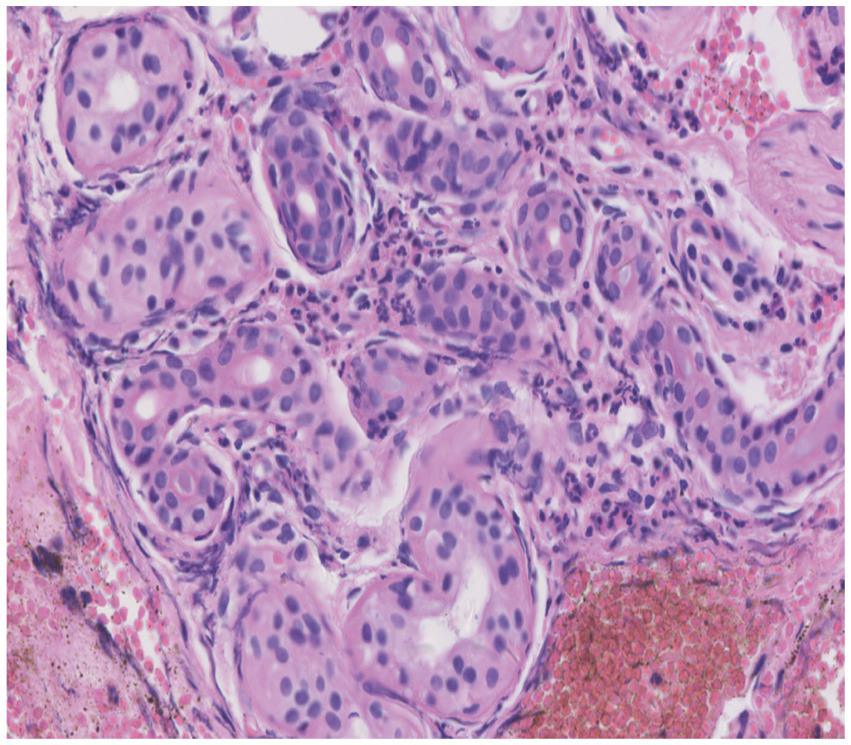

Skin tissue biopsy showed histopathological changes in the skin, where the epidermis showed mild vacuolar degeneration and varying numbers of neutrophil infiltrates just beneath the surface of the deep dermis—primarily the superficial dermis—as well as cavernous pustules under the epidermis; an example of these changes is presented in Figure 2. We performed whole exome sequencing and Sanger validation on all five patients and identified CARD14 gene mutations in three patients. Seven mutation sites were detected: c.1641G > C (p.Arg547Ser) heterozygous mutation, c.2422A > G (p.Thr808Ala) heterozygous/homozygous mutation, c.2458C > T (p.Arg820Trp) heterozygous mutation, c.1323C > T (p.Asp441Asp) heterozygous mutation, c.633G > A (p.Glu211Glu) heterozygous mutation, c.1753G > A (p.Val585Ile) heterozygous mutation, and c.2481C > T (p.Pro827Pro) heterozygous mutation (Figure 3). No mutations were identified in the IL-36RN gene.

Figure 2

Histopathological examination of a skin biopsy from the left chest showed mild vacuolar degeneration of epidermal basal cells, varying numbers of neutrophil infiltrates in the superficial-deep dermis (mainly in the superficial dermis), and epidermal cavernous pustule formation (hematoxylin and eosin staining; original magnification, ×400).

The typical manifestations of AGEP include tens to hundreds of non-follicular pinhead-sized sterile pustules that appear rapidly as edematous erythema, generally originating on the face or intertriginous areas of the body, and rapidly spreading to the trunk and limbs. Histopathology on sub-corneal pustules located in the superficial layer of the epidermis reveals the presence of immune cells—mainly neutrophils and occasionally eosinophils—and an almost unchanged epidermis below the pustules, showing only infiltrated neutrophils and mild intercellular edema (2). In the five patients we reported, the rash initially appeared on the cheeks and facial area, joints of the extremities, scalp, and hands. Afterward, the rash spread rapidly to other parts of the body. All cases had facial involvement, which is consistent with the clinical presentation of AGEP. HCQ-related AGEP can be clearly distinguished from GPP—which recurs often—and there may be typical psoriasis lesions before the appearance of pustules; these appear on the original plaque or rash and can expand and fuse to form “pus lakes.” In addition, some patients with GPP have a family history, and the histopathological manifestations are psoriasis-like hyperplasia of the epidermis with keratosis, Kogoj micro-abscesses in the upper part of the spinous layer, and superficial dermal telangiectasia and tortuous vessels (58). In this sample, there was no family history of psoriasis, the rash appeared after HCQ treatment, and pustule formation was observed on histopathology, which is not the case in patients with GPP. Therefore, patients with suspected HCQ-induced AGEP may benefit from histopathology and skin biopsy.